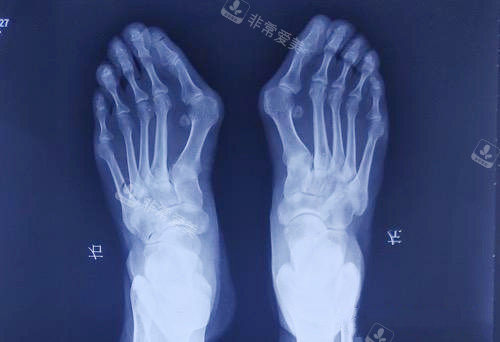

大脚骨拍片